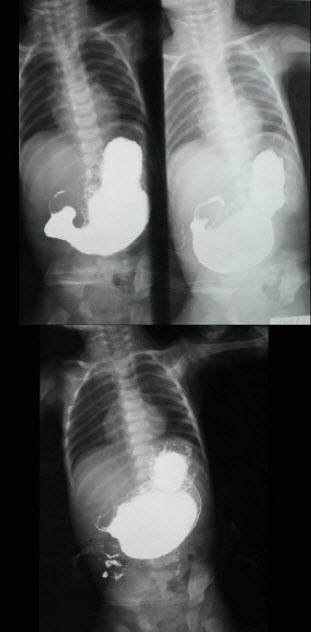

193、单项选择题

男,6月。出生1月后经常出现喷射状呕吐,为奶块,渐加重。面色消瘦,右上腹部可触及核桃大小硬块。如图,最可能的诊断为()

A.胆总管囊肿

B.肠闭锁

C.先天性幽门肥厚狭窄

D.肠套叠

E.先天性巨结肠

点击查看答案